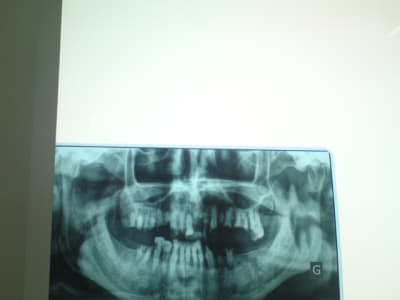

Faut voir le sujet ou une pano pour en discuter.

décidément sans radio impossible de dire quoi que ce soit

désolée pour la qualité de l'image

Tu as raison en haut complet

En bas , faut voir en bouche l'état et ce que veux le sujet , prise de conscience du pb , volonté de s'investir, je garderai de la 33 à 43 le reste saute, et tu vois selon ses désirata ou ses moyens P adjointe ou fixe plus cher et la ca m'étonnerait qu'il veuille suivre .